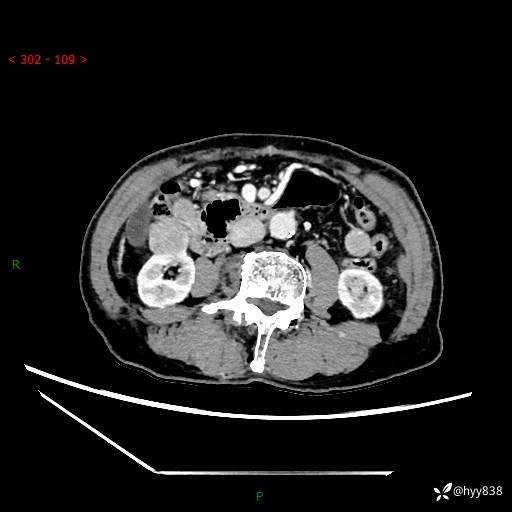

辅助检查:CT

临床诊断:肾肿物

肾脏CT平扫

增强(皮质期+髓质期+排泄期)

三期CT值:132hu 107hu 81hu